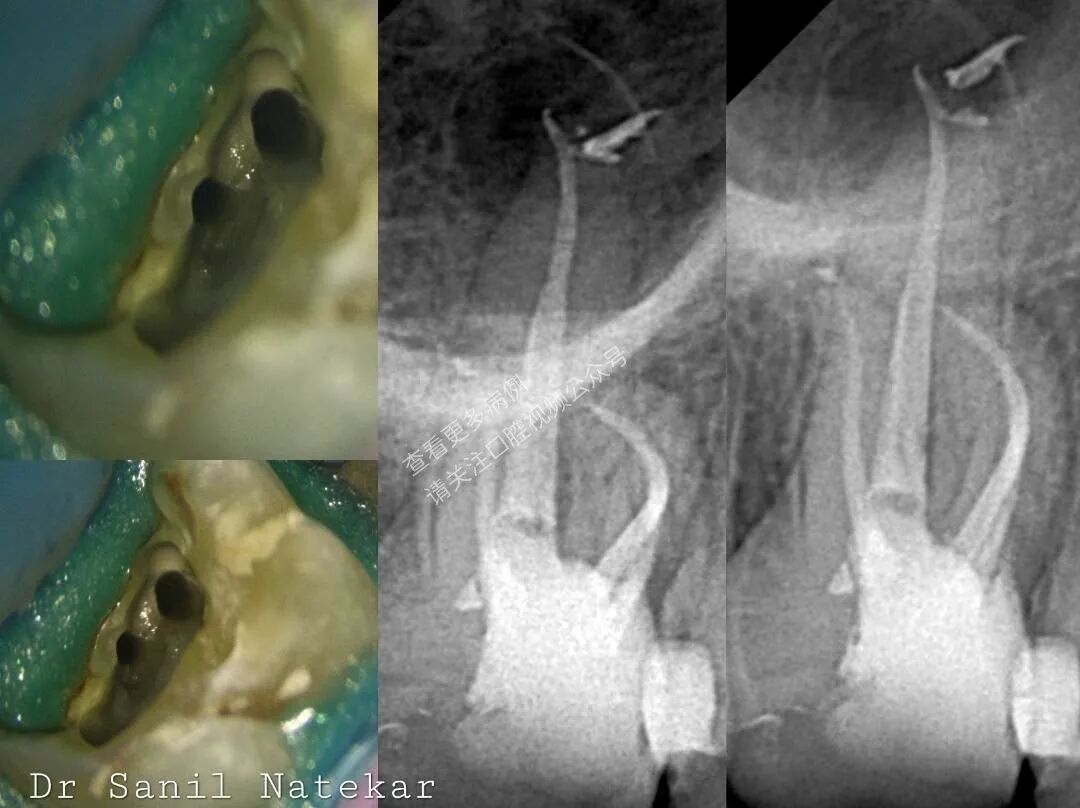

在根管治疗中,MB2根管(近中颊侧第二根管)的遗漏仍是持久难题。更复杂的是,当MB2在根中部(mid-root level)时,常规器械难以顺利进入与成形,显著增加治疗失败风险。

传统定位法(如DB-P线法或MB-P垂线法)常仅提供一个区域范围,而非精确点位。Dr. Wang提出一种联合几何定位法,显著提高可预测性:

定位原理:MB2的预测位置 =① 过MB点作一条平行于DB–P连线的直线与② 从DB点向MB–P连线所作垂线的交点。

该方法通过融合两种经典技术的优势,克服了单一方法仅能界定“可能区域”的局限,实现更精准的点位预测。